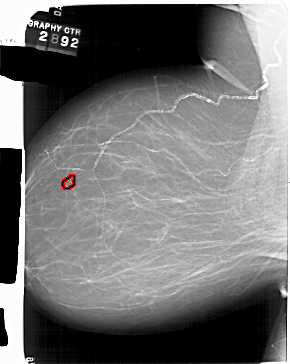

A_1551_1.LEFT_MLO

LEFT_CC LINES 6346 PIXELS_PER_LINE 4876 BITS_PER_PIXEL 12 RESOLUTION 43.5 OVERLAY

FILE: A_1551_1.LEFT_MLO.OVERLAY

TOTAL_ABNORMALITIES 1

ABNORMALITY 1

LESION_TYPE CALCIFICATION TYPE PLEOMORPHIC DISTRIBUTION CLUSTERED

ASSESSMENT 4

SUBTLETY 4

PATHOLOGY BENIGN

TOTAL_OUTLINES 1

BOUNDARY